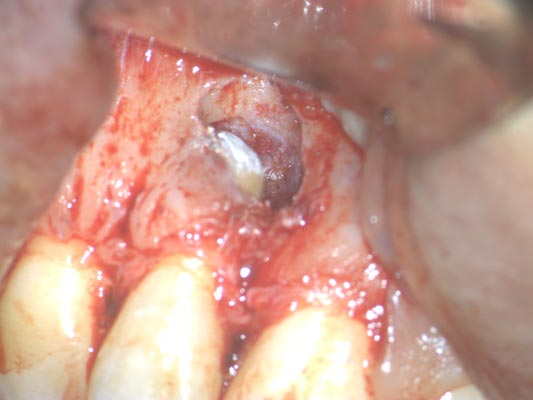

Microcirugía Periapical

La microcirugía periapical o retratamiento retrógrado es una opción terapéutica poco invasiva indicada en aquellos casos en los que la endodoncia o la reendodoncia no han evolucionado favorablemente.

El procedimiento consiste en realizar un acceso quirúrgico al extremo de la raíz (ápice), resecar aproximadamente 3mm del extremo radicular, eliminar el material de obturación presente en esa zona y colocar un material sellador biocompatible que permita un cierre adecuado del conducto desde su porción final.

Antes de llevar a cabo la intervención, es imprescindible realizar una valoración mediante CBCT para estudiar la anatomía y planificar el tratamiento con precisión.

Para garantizar la exactitud del procedimiento y mejorar el pronóstico, la microcirugía apical debe realizarse con microscopio dental, que permite trabajar con magnificación e iluminación adecuadas en un campo quirúrgico reducido.

Imágenes:

Radiografía previa y final del tratamiento.

Medimos el ápice, retiramos el relleno anterior y colocamos relleno biocompatible.